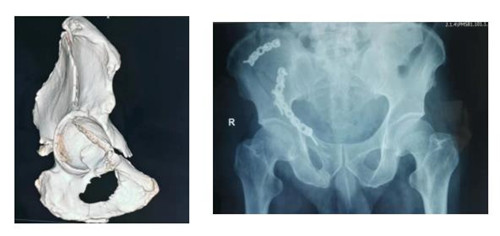

10月5日,乐鱼在线登录入口骨三科收住一位不同寻常的患者。该患者自1.5米高处坠落,右髋部着地,致右髋部持续剧烈疼痛,不能行走站立,被他人救起送往就近医院。行X线、CT检查示:右髂骨、髋臼、耻骨升降支多发骨折。因手术难度较大,患者家属辗转渭南各医院,经多方打听胡洪波副主任医师在骨盆髋臼骨折治疗方面颇有经验,特前来我院。

接诊该病人后胡洪波副主任前往CT室对骨折移位情况进行分析、定位。经过详细询问病史、查体,结合检查结果,骨三科团队确定采用经腹旁外侧入路为患者进行手术。手术耗时短,出血少,骨折复位满意,固定可靠,患者和家属对治疗效果十分满意。

骨盆髋臼骨折腹旁外侧入路也是胡洪波副主任在骨盆髋臼骨折领域继stoppa入路之后带来了第二个新的手术入路。腹旁外侧入路是进行髋臼前柱骨折的新的手术入路方式,此入路临近血管、神经、腹膜等重要器管,所以临床中还未能广泛开展。但因为此入路具有切口小、创伤少、患者恢复快等巨大优点,近年来已逐渐应用于临床,为骨盆髋臼骨折患者的快速康复带来了福音。